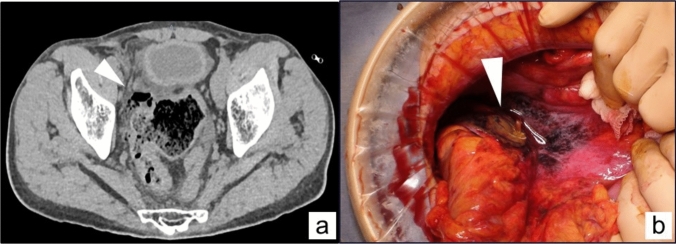

Results: The patient underwent Hartmann's procedure for generalized peritonitis resulting from perforation of the sigmoid colon. The abdominal cavity was significantly contaminated with fecal ascites, and postoperative pelvic adhesions were anticipated. Therefore, the rectal stump was lifted. The outcomes demonstrated that despite the presence of dense adhesions in the abdominal cavity, the rectal segment was promptly identified during the reversal of Hartmann's procedure. The procedure proceeded smoothly and was deemed satisfactory.